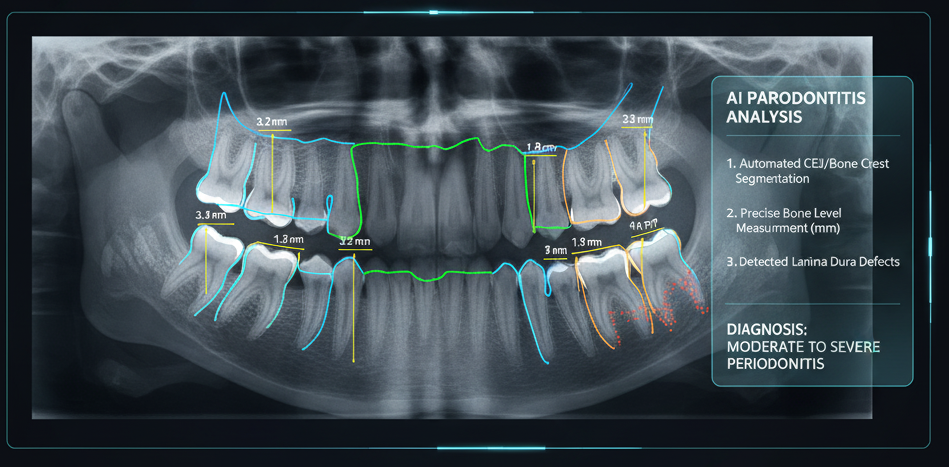

2. Rilevamento di Lesioni Ossee Minime (Parodontite)

La diagnosi precoce della parodontite si basa sull’identificazione di una perdita ossea minima, spesso di frazioni di millimetro, un compito che richiede grande esperienza e misurazioni precise.

L’IA automatizza e sovralimenta questo processo:

- Segmentazione Anatomica Automatica: Per prima cosa, l’IA identifica e “segmenta” (cioè traccia i contorni esatti) delle strutture chiave in automatico: la radice del dente, la Giunzione Amelo-Cementizia (CEJ) e l’attuale cresta dell’osso alveolare.

- Misurazione Sovrumana: Una volta identificate queste linee, l’algoritmo esegue una misurazione iper-precisa, a livello di sub-pixel, della distanza tra la CEJ e la cresta ossea in più punti lungo il dente.

- Identificazione di Pattern Sottili: L’occhio umano cerca principalmente una distanza “aumentata”. L’IA, invece, cerca anche altri segni precoci che ha imparato a correlare alla malattia:

- Perdita della Lamina Dura: Rileva la sfocatura o l’assottigliamento della lamina dura (la sottile linea bianca di osso compatto che circonda la radice del dente), un segnale precoce di infiammazione e riassorbimento osseo.

- Variazioni nella Trabecolatura: Analizza la struttura a “rete” dell’osso (pattern trabecolare). Può identificare se gli spazi tra le trabecole stanno diventando più grandi o se il pattern sta cambiando, indicando un processo di riassorbimento attivo prima ancora che il livello osseo verticale sia sceso visibilmente.

In entrambi i casi, il vantaggio dell’IA è la sua oggettività e la sua sensibilità. Non è soggetta ad affaticamento visivo e non interpreta le immagini: le analizza matematicamente, confrontando milioni di micro-pattern per trovare anomalie statistiche che corrispondono a patologie note, spesso molto prima che diventino evidenti per un osservatore umano. In sostanza un software basato su IA può evidenziare aree sospette su una radiografia che richiedono ulteriore attenzione, portando a interventi meno invasivi.

1. Misurazione Automatica della Perdita Ossea (Parodontite)

Questa è una delle applicazioni più potenti dell’IA in parodontologia. Utilizzando radiografie (panoramiche, bitewing o periapicali) e CBCT, l’algoritmo esegue i seguenti passaggi in pochi secondi:

- Segmentazione Anatomica: L’IA identifica e traccia automaticamente i contorni di strutture anatomiche chiave: la radice del dente, la Giunzione Amelo-Cementizia (CEJ) e la cresta ossea alveolare (il livello attuale dell’osso).

- Misurazione di Riferimento: Misura la lunghezza totale della radice.

- Calcolo della Perdita Ossea: Misura la distanza esatta (in millimetri o pixel) tra la CEJ (il punto di riferimento standard) e il livello attuale della cresta ossea.

- Classificazione: Confrontando la perdita ossea con la lunghezza totale della radice, l’IA calcola la percentuale di perdita ossea per ogni singolo dente. Può così classificare automaticamente lo stadio della parodontite (es. lieve, moderata, grave) e segnalare al dentista le aree più critiche.

Il vantaggio: L’IA elimina la soggettività e la variabilità della misurazione manuale, fornendo un dato oggettivo, riproducibile e quasi istantaneo.